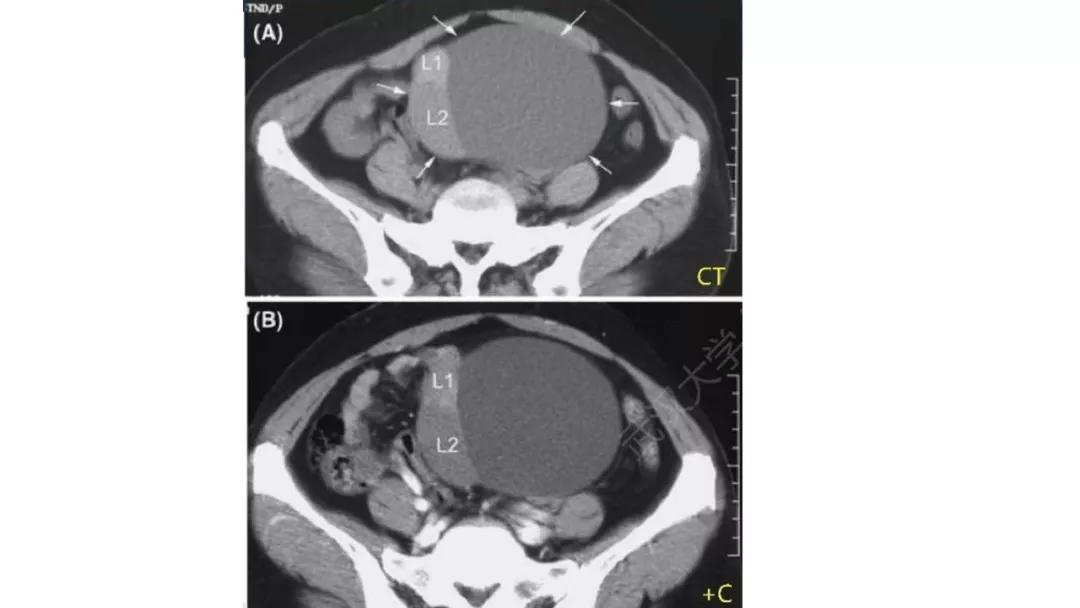

病理:浆液性囊腺癌